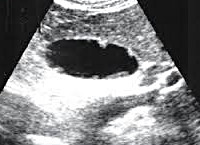

Основной метод диагностики, с помощью которого выявляют холестероз, - УЗИ желчного пузыря. Эхографическую картину изменений можно наблюдать только на переднебоковой стенке, так как даже на современной аппаратуре получить картинку задней стенки достаточно трудно. Холестероз желчного пузыря на УЗИ выявляется в виде утолщения стенок, чаще неравномерного. При диффузной форме можно увидеть отдельные эхопозитивные участки в виде пунктирной линии. Полипозная и очаговая форма диагностируются легче, они визуализируются в виде отдельных пристеночных образований или локальных утолщений стенки пузыря.

Для усиления сигнала и улучшения диагностики используют метод межреберного и мультипозиционного сканирования. Также дополнительно усиливают сокращение желчного пузыря с помощью желчегонного завтрака. Это позволяет лучше визуализировать изменения стенок и увидеть нарушения сократительной способности.